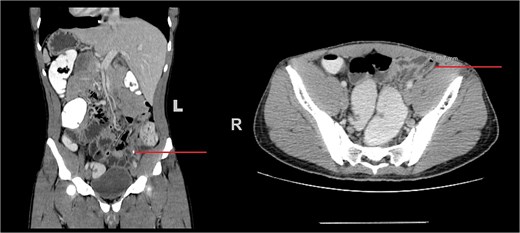

Laboratory tests showed white blood cell count 13.2 × 109/L; LFTs and renal profile were normal. Inflammatory markers C-reactive protein, erythrocyte sedimentation rate were not requested. A chest X-ray revealed dextrocardia, raising suspicion for SIT. Abdominal X-ray was unremarkable. Contrast-enhanced computed tomography (CT) confirmed SIT with the appendix in the left iliac fossa, measuring 11 mm with mural thickening, intraluminal appendicolith, and peri-appendiceal fat stranding—consistent with early acute appendicitis (Fig. 1).

Coronal (left) and axial (right) CT images of the abdomen demonstrating situs inversus totalis with the liver located on the left side and spleen on the right. The inflamed appendix is seen in the left iliac fossa, with mural thickening and a visible appendicolith (arrow), consistent with acute appendicitis.